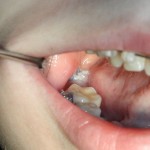

Через два дня послеоперационная рана выглядит следующим образом:

Как понимаете, пациентку ничто не беспокоит. Ну, разве, что отек немного. Он сойдет через 3-4 дня, и она спокойно продолжит работу со своим врачом-ортодонтом.